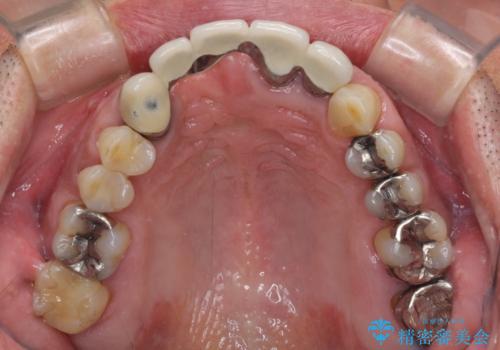

- 前歯のブリッジのせいで話しにくく、金属の縁などが露出して見栄えが悪いので、作り直したいとのことで来院された患者様です。

土台となる歯は根管治療の結果が良好ではないため、根管治療からやり直しをした後、オールセラミックブリッジにて補綴することとしました。

露出していた歯根や金属の縁が見えてしまい、人前で話すときの目線が気になっていらっしゃいましたが、歯肉の位置に縁を合わせてことで自然な仕上がりとなりました。

露出していた歯根が覆われるため、歯冠が長く見えてしまうことが懸念されましたが特に気になることはなく、患者様には大変満足していただきました。